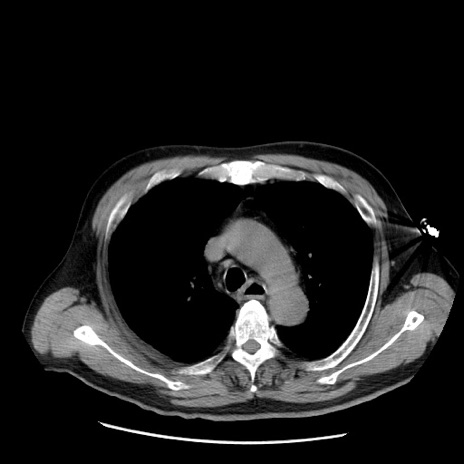

症例20(横断像)

【症例】 60歳代男性

【主訴】 腹部膨満、嘔吐

【現病歴】5日前頃より倦怠感を認め食事量減少し4日前の朝嘔吐、食事摂取困難となった。 3日前近医受診し点滴施行され整腸剤などを処方された。 当日他院を受診し、腹部膨満著明、炎症反応の上昇(CRP10.8、WBC11200)あり、紹介受診となる。

【身体所見】 意識JCS1 受け答えがはっきりしないBP 111/57mHg、 P 67bpm、、BT35.2°C、SpO2 97%(RA)、 腹部:膨隆、打診で鼓音あり、全体的に圧痛有り、腸蠕動音(-)、反跳痛ははっきりせず。

【データ】WBC 11400、CRP 14.20